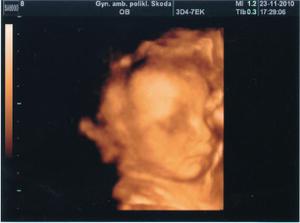

23.11. 3D UTZ na poliklinice Škodovky v Mladé Boleslavi. Byl to úžasný zážitek. Malá se hezky ukázala, má 681g. Všechny míry jsou v normě. Už víme, že nosík má po mamince a bradičku po tatínkovi🙂